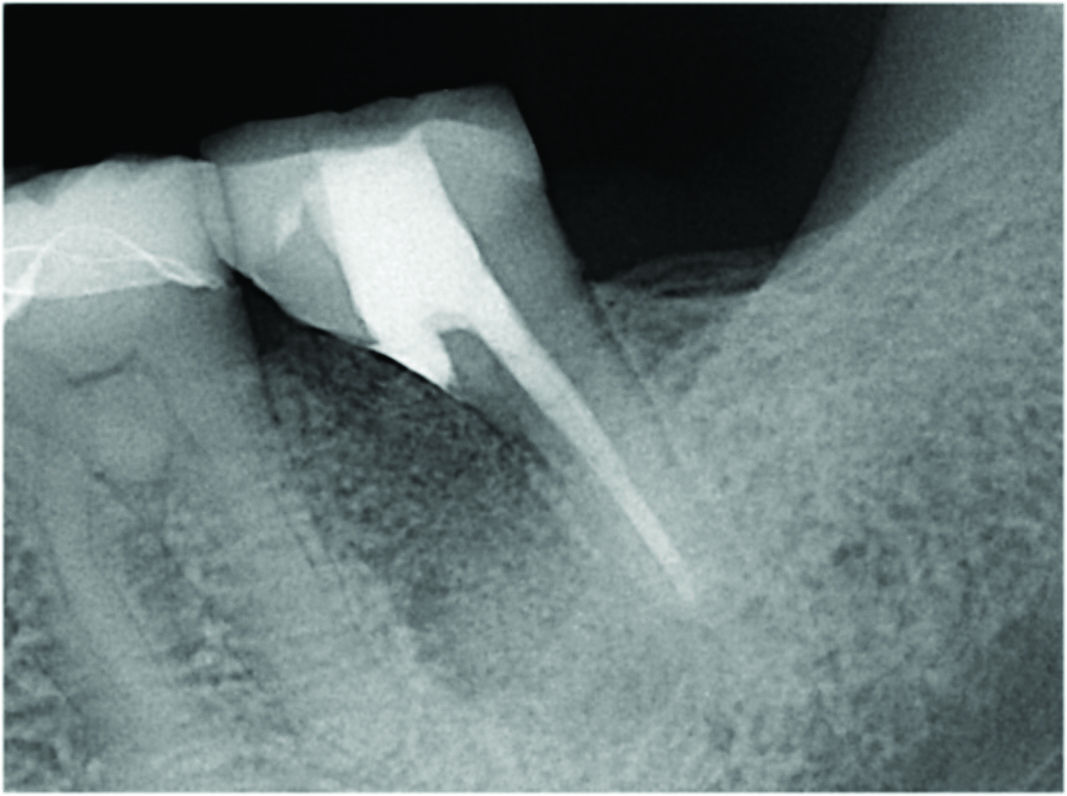

As clinically observed by the authors, most root resection cases in which a graft is placed (see "Graft Placement" below) will heal over time with the crestal bone stabilizing at a point that is 1 mm to 3 mm below the cantilevered portion of the tooth. This fact reinforces the importance of having a more coronal resection level and not leaving a stub of the resected root; a stub will extend further apically and over time result in greater crestal bone loss and future problems related to plaque control and periodontal issues. The case shown in Figure 8 is a 5-year post-treatment image of tooth No. 30, depicting the anticipated healing outcome of a grafted resected root socket. It demonstrates the result of well-managed plaque control and optimally maintained crestal bone.

Fig 8. A cleansable resected root surface, the root filling, and the root contour will affect the prognosis. Fig 5: Tooth No. 19 at 1-year post-treatment with a remaining stub of the mesial root following root resection; note a subsequent larger-than-expected crestal bone loss defect below the cantilevered portion of the tooth. Incomplete resection and lack of proper contour toward the mesial contact has created a plaque trap and subsequent unstable periodontal status. This problem can be avoided with a more aggressive resection to ensure a cleansable situation. Fig 6: Clinical image of tooth No. 14 with a resected mesiobuccal root and RMGI restoration of the underside of the tooth. The resultant contour has no lips or ridges and has a smooth transition to the mesial contact space; there is also a smooth transition to the remaining distobuccal and palatal roots, creating a cleansable situation. Fig 7: Tooth No. 18 immediately following resection of the mesial root demonstrates a contoured mesial surface that smoothly blends to the mesial contact region. The underside of the cantilevered portion of the tooth is restored with a RMGI restoration, and the socket is grafted with an allograft.

Fig 8: Tooth No. 30 with a resected mesial root and restoration of the underside with a RMGI restoration at 5 years post-treatment is displaying the expected healing pattern of the crestal bone following grafting of the socket. The proper resection and contouring permits adequate maintenance and resultant stability of the tooth.